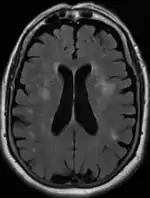

Leukoaraiosis is a particular abnormal change in appearance of white matter near the lateral ventricles. It is often seen in aged individuals, but sometimes in young adults.[1][2] On MRI, leukoaraiosis changes appear as white matter hyperintensities (WMHs) in T2 FLAIR images.[3][4] On CT scans, leukoaraiosis appears as hypodense periventricular white-matter lesions.[5]

The term "leukoaraiosis" was coined in 1986[6][7] by Hachinski, Potter, and Merskey as a descriptive term for rarefaction ("araiosis") of the white matter, showing up as decreased density on CT and increased signal intensity on T2/FLAIR sequences (white matter hyperintensities) performed as part of MRI brain scans.

These white matter changes are also commonly referred to as periventricular white matter disease, or white matter hyperintensities (WMH), due to their bright white appearance on T2 MRI scans. Many patients can have leukoaraiosis without any associated clinical abnormality. However, underlying vascular mechanisms are suspected to be the cause of the imaging findings. Hypertension, smoking, diabetes,[3] hyperhomocysteinemia, and heart diseases are all risk factors for leukoaraiosis.